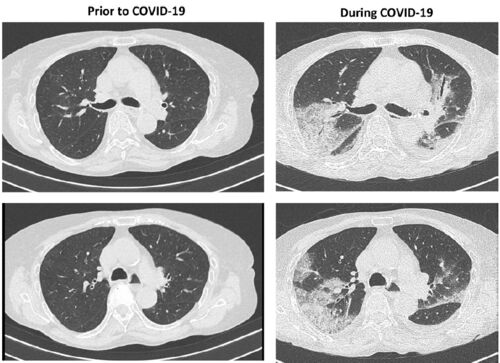

COVID-19の重症肺炎が遅れて発症した?リツキシマブで治療中の強皮症の3症例

#リツキシマブはB cell depletionという、CD20を表現するB細胞を除去する機能を持つ薬剤です。つまり、この薬剤で治療中の患者はウイルス感染の免疫システムである抗体産生が上手くできない恐れがあります。 この度はリツキシマブを使用中にCOVID-19を発症…